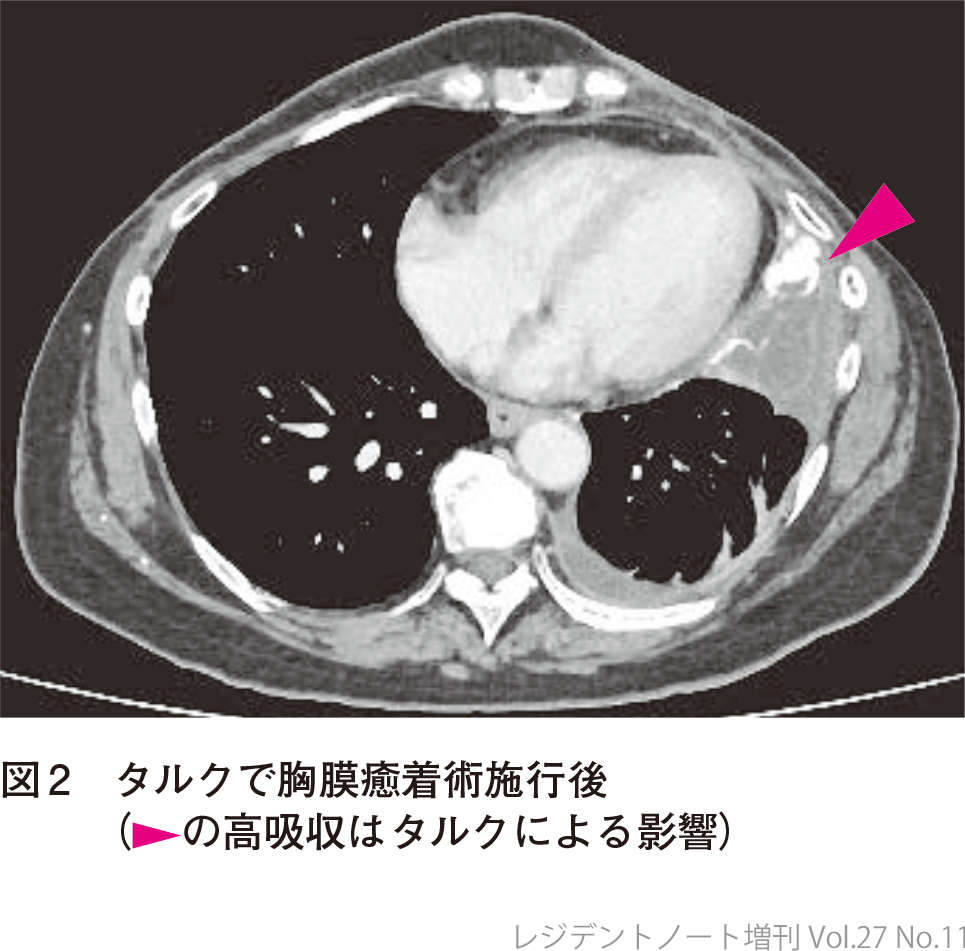

2) 胸膜癒着術

胸腔ドレーンやアスピレーションキットで胸水ドレナージが十分にでき,肺の拡張が得られた場合,胸膜癒着術が検討される.胸膜癒着術は,薬剤を胸腔内に注入して臓側胸膜と壁側胸膜に炎症を起こさせることで癒着させ,その後の胸水貯留を抑える方法である.予後3カ月未満が予想される場合や,虚脱肺(trapped lung)を伴う場合は,一般的には胸膜癒着術の適応にはならない.

使用する薬剤はタルクがほかの薬剤に比較して有効性が高く4),当院でも基本的にはタルクを用いて胸膜癒着術を施行する.手技の詳細に関しては誌面の都合上,本稿では割愛させていただく.

悪性胸水の診断で,胸水以外の病変は増大なく経過していたことから胸膜癒着術を施行する方針とした.胸腔ドレーンを挿入して連日排液を行い,十分に排液できたことを確認してタルクで胸膜癒着術を施行.その後も胸水増加みられず,胸腔ドレーンは抜去.以降も胸水増加なく経過している(図2).